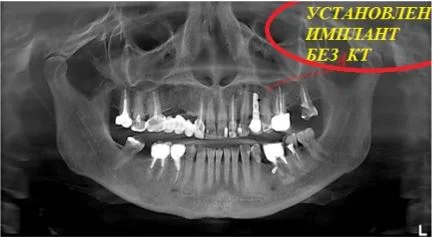

Компьютерная томография - это ключевой метод обследования в имплантологии

Воссоздавая орган (зуб) или даже совокупность органов, необходимо предельно точно знать исходную ситуацию. Корни зубов, каналы зубов, крупные сосудисто-нервные пучки, идущие внутри костной ткани, верхнечелюстная пазуха во всех подробностях и т.д. - в неискаженном виде все это можно увидеть только на компьютерной томограмме. Стоит ли говорить, что все эти структуры важны для имплантации, так как могут быть легко поврежденфы в ходе операции.

Как получить гарантированный результат имплантации? При помощи компьютерной томографии!